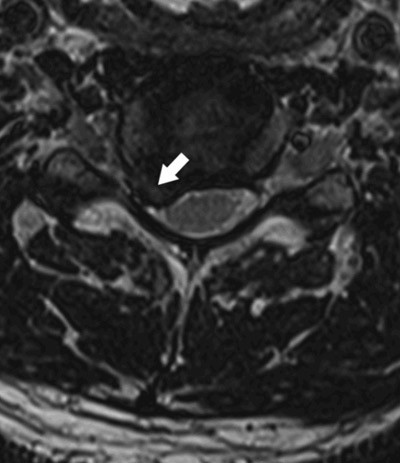

Annulusrupturer er konsentriske eller radiære sprekker i anulus fibrosus. De ses på T2-vektede MR-bilder som områder med høyt signal i kanten av skiven (high intensity zone, HIZ), typisk i midtlinjen inn mot spinalkanalen i de nederste lumbale skivene (fig 2). Det har vært hevdet at annulusruptur kan gi ryggsmerter gjennom enten direkte mekanisk påvirkning av smerteførende fibre i kanten av skiven eller ved lekkasje av inflammatorisk aktive substanser fra nucleus pulposus (13). Imidlertid er dette et hyppig funn også hos asymptomatiske personer. I en normalpopulasjon av 40-åringer i Danmark (15) hadde ca. 40 % annulusruptur, og det var bare en moderat assosiasjon med kroniske ryggsmerter. Funn av slike rupturer på MR-bilder må ses som en del av utviklingen av skivedegenerasjon, men funnet i seg selv kan ikke tillegges noen vesentlig betydning som årsak til symptomer.